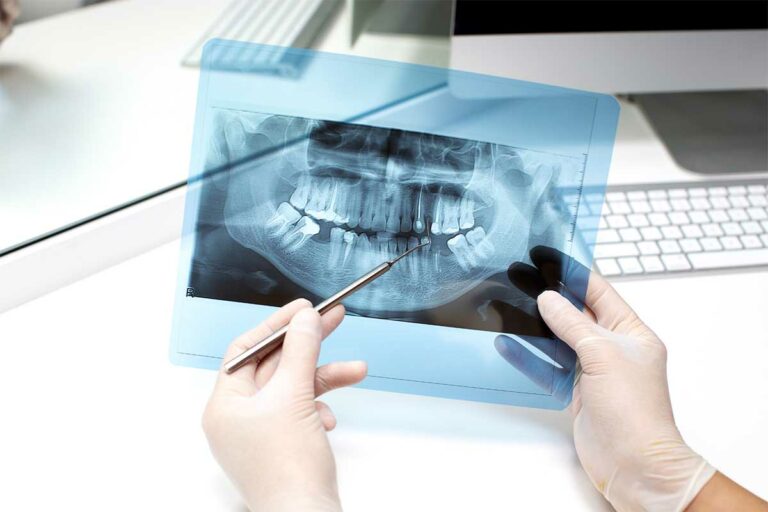

Präzise Planung mit 3D-Technologie

Mithilfe moderner 3D-Diagnostik (DVT/CT) planen wir Ihre Implantatbehandlung präzise am Computer. Auf Basis dieser Planung kann eine 3D-gestützte Operationsschablone gefertigt werden, die eine exakte und sichere Implantation ermöglicht.